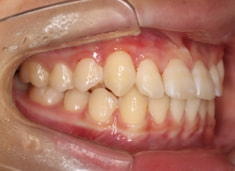

FX(フェイシャルアキシス)は85度なので東洋人の平均値に近く、下顎が前方に過剰成長するリスクは強くはありません。

しかしやはり上顎は劣成長で、下顎が優位な状態ではあります。

上下顎のギャップはありますが、顔面自体の幅径は良好な値を示していますので、スペース不足は拡大することによって解決できポテンシャルはあると考えられます。

左右の非対称もさほど強くありません。

骨年齢は実年齢よりも低めなので、今後下顎の旺盛な成長が見込まれます。